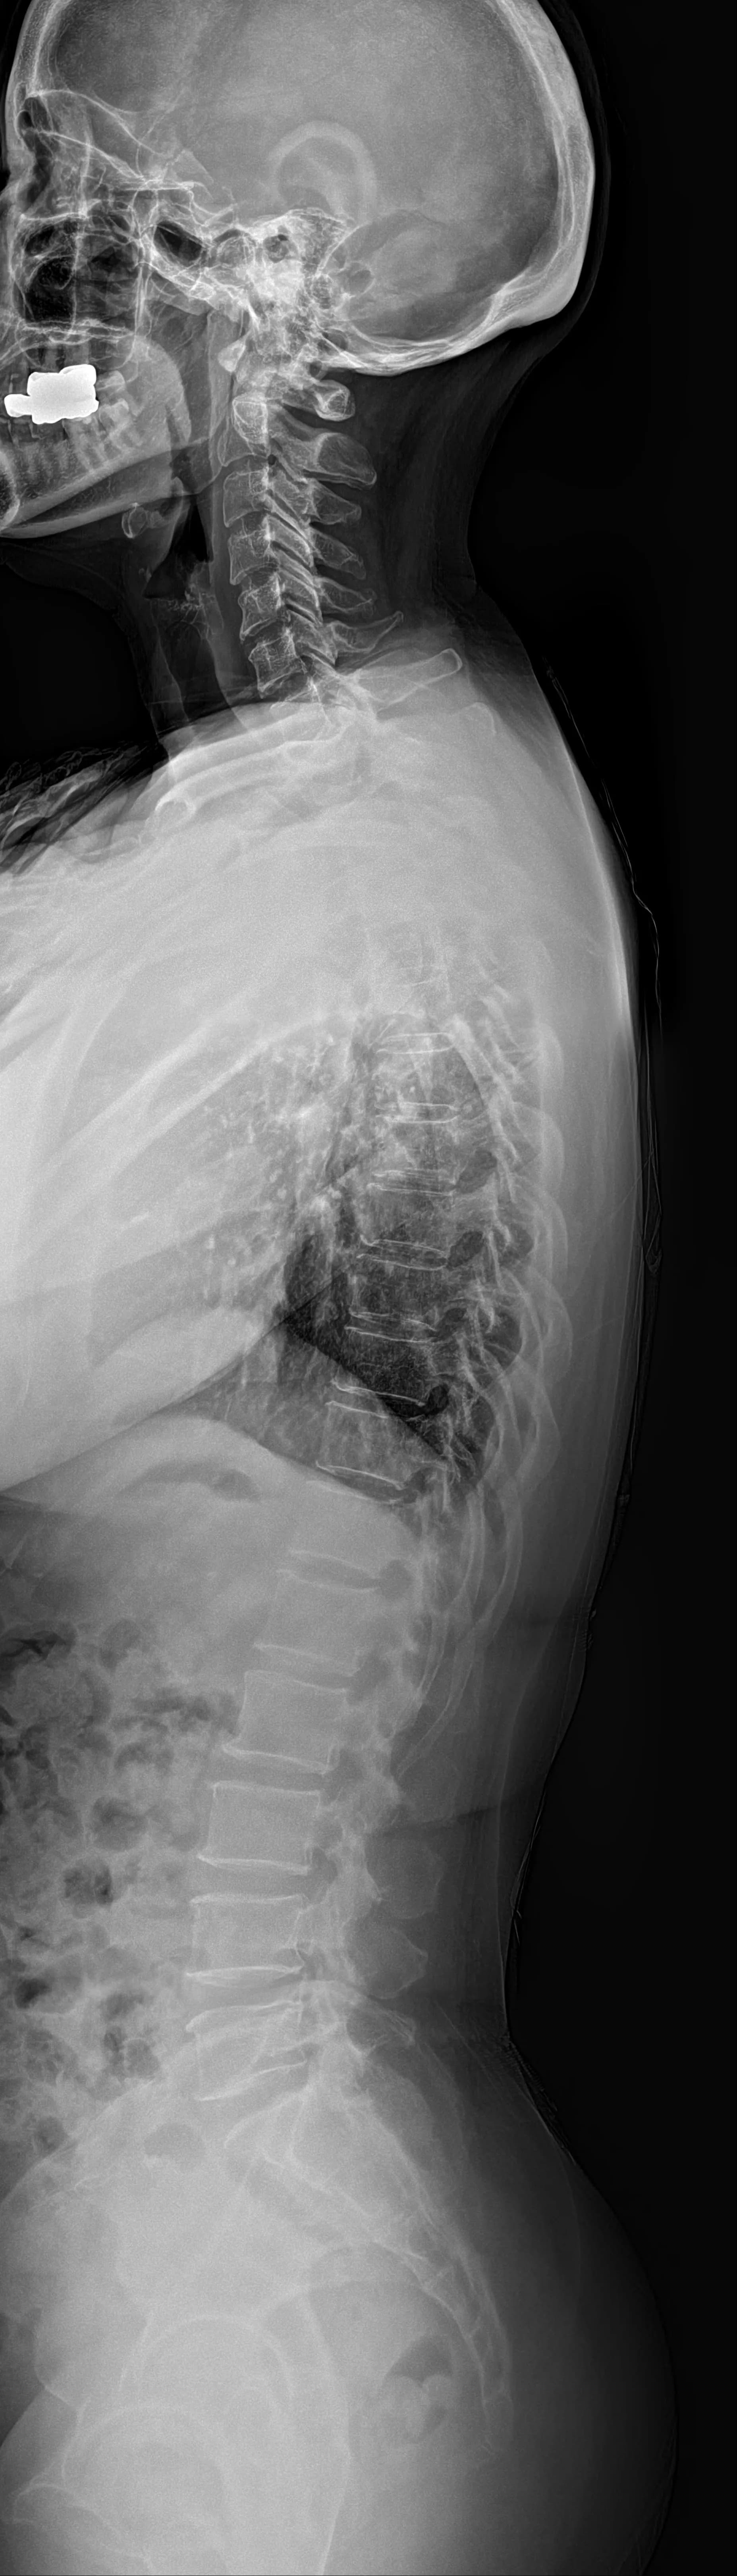

Musculoskeletal X-ray AI Analysis

부위를 클릭하여 결과 이미지를 확인하실 수 있습니다.